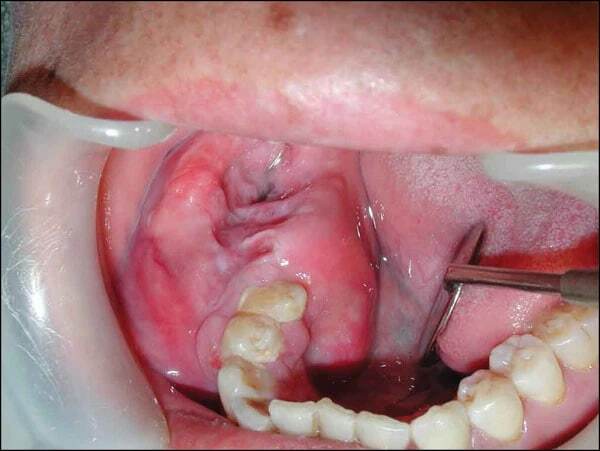

Амелобластома

Амелобластома представляет собой редкую доброкачественную опухоль, которая в основном располагается в задних отделах нижней челюсти, вызывающую деструкцию костных тканей.

Поначалу отмечается полное отсутствие выраженных симптомов до тех пор, пока опухоль не станет больше. Типичными проявлениями являются: аномальный рост в области челюсти или носовых пазух; безболезненный отек челюсти; боль в костях; задержка прорезывания зубов; обструкция носовых дыхательных путей; язвы во рту; неправильное положение зубов при смыкании челюсти; ассиметричность лица.

Диагностика затруднена на ранних стадиях, постановка диагноза основана на данных цитологического исследования, компьютерной томографии, рентгенографии.

Лечение заключается в широком иссечении и при необходимости реконструкции.